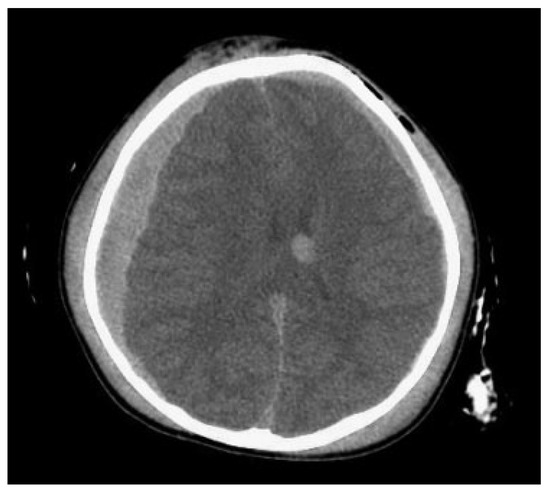

The disparity between craniofacial fracture patterns in children and adults may present different complication profiles. Many studies have shown that pediatric facial trauma shares a strong association with concomitant extra-facial head and neck injury [3,5,9,10,11]. One complication of particular importance is intracranial hemorrhage (ICH), which has been well documented to occur in association with facial fractures [12,13,14]. ICH is an important complication to recognize, as it can cause death or lifelong disability in children (Figure 1). Though possible causes include brain tumors, congenital heart disease, and vascular lesions, the most common cause of ICH in children, and the one with the highest associated morbidity and mortality, is trauma [15,16]. Because ICH at an early age is associated with developmental delay, cerebral palsy, epilepsy, and death, early recognition is imperative. Presenting signs include mental status changes, headaches, convulsions, focal neurological deficits, and vomiting [15]. Specifically, skull fracture, focal neurological deficit, seizure, and Glasgow coma scale (GCS) < 15 were all significantly correlated with ICH according to a 2014 meta-analysis investigating the association of particular symptoms to ICH in pediatric patients with minor head trauma. The utility of the GCS was further corroborated by a study showing a very low incidence of ICH in pediatric patients with minor head trauma and a GCS of 15 [17]. Important considerations in management include GCS, type of hemorrhage, and presence of high-risk comorbidities. Intraventricular hemorrhage, epidural hematoma, and comorbidities such as shunted hydrocephalus and arteriovenous malformation have been implicated in radiologic progression of hemorrhage, and are therefore indications for monitoring in an intensive care setting [18].

Figure 1.

A 2-year-old child with significant intracranial injury following a fall.